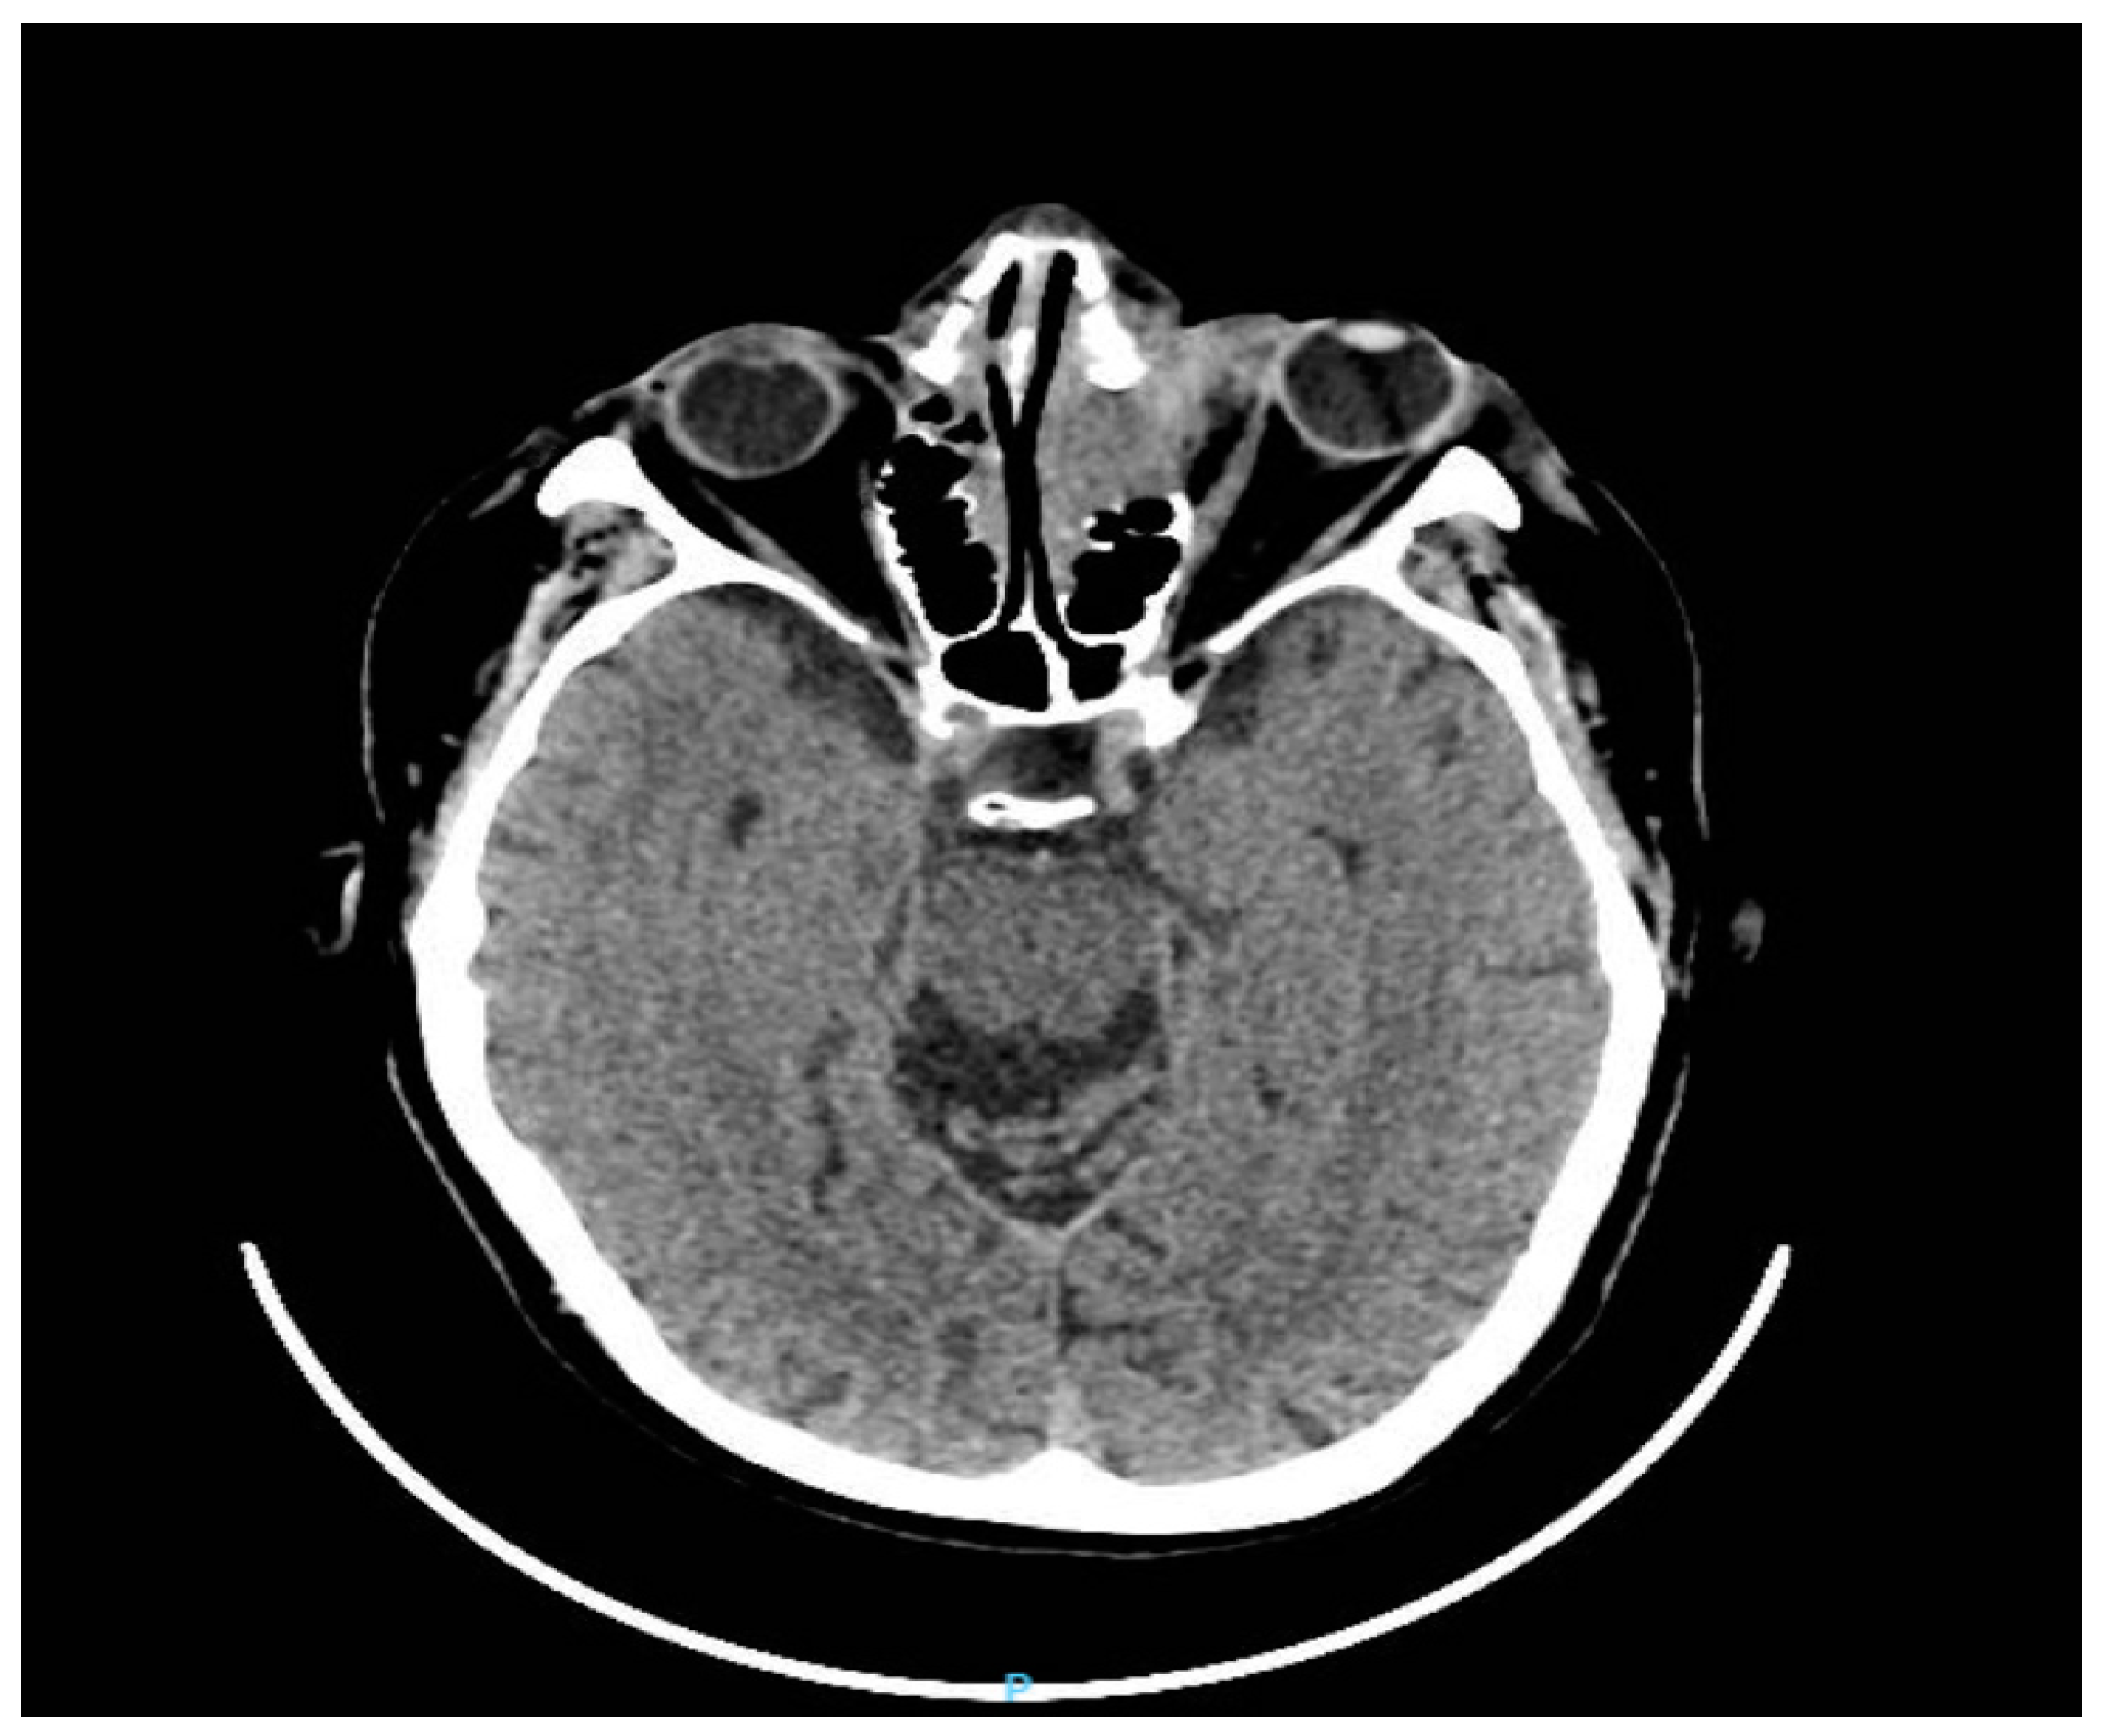

Figure 3.

Computed tomography of the brain and orbit (axial planes) showed a front-ethmoid tissue mass with bone destruction and regional invasion with the left orbital extension in contact with the eyeball and left frontal intracranial extension of approximately 3.8/4/4.2 cm. The patient’s treatment began with maximal topical anti-glaucoma eye drops (topical beta-blockers, alpha-agonists, and carbonic anhydrase inhibitors). The patient’s care was subsequently co-managed with the oncological team. He started radiotherapy sessions according to the Intensity Modulated Radiation Therapy (IMRT)) scheme with a total dose of 30 Gy in 15 fractions given in 3 weeks and 2Gy/fraction. The irradiation was done with a thermoplastic mask after a CT planning where the tumor mass and adjacent structures were contoured (red color). Radiation doses delivered to normal anatomical structures (optic nerves, the lens) were within parameters (Figure 4).